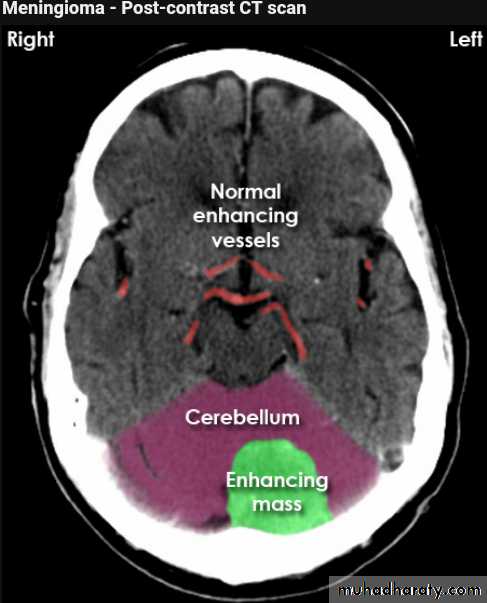

CT finding

meningioma presented as isodense area or slightly hyper density area with surrounded crescent of hypo density ( csf cap ) post contrast injection the lesion enhance homogeneously with enhancing Dural tail .

20 % show calcification

hyperostosis & thickening of the near by bony part of the skull & diplioc space .

it may be associated with little or no peri focal edema .

if the lesion associated with central necrosis with large perifocal edema meningio sarcoma should be excluded .